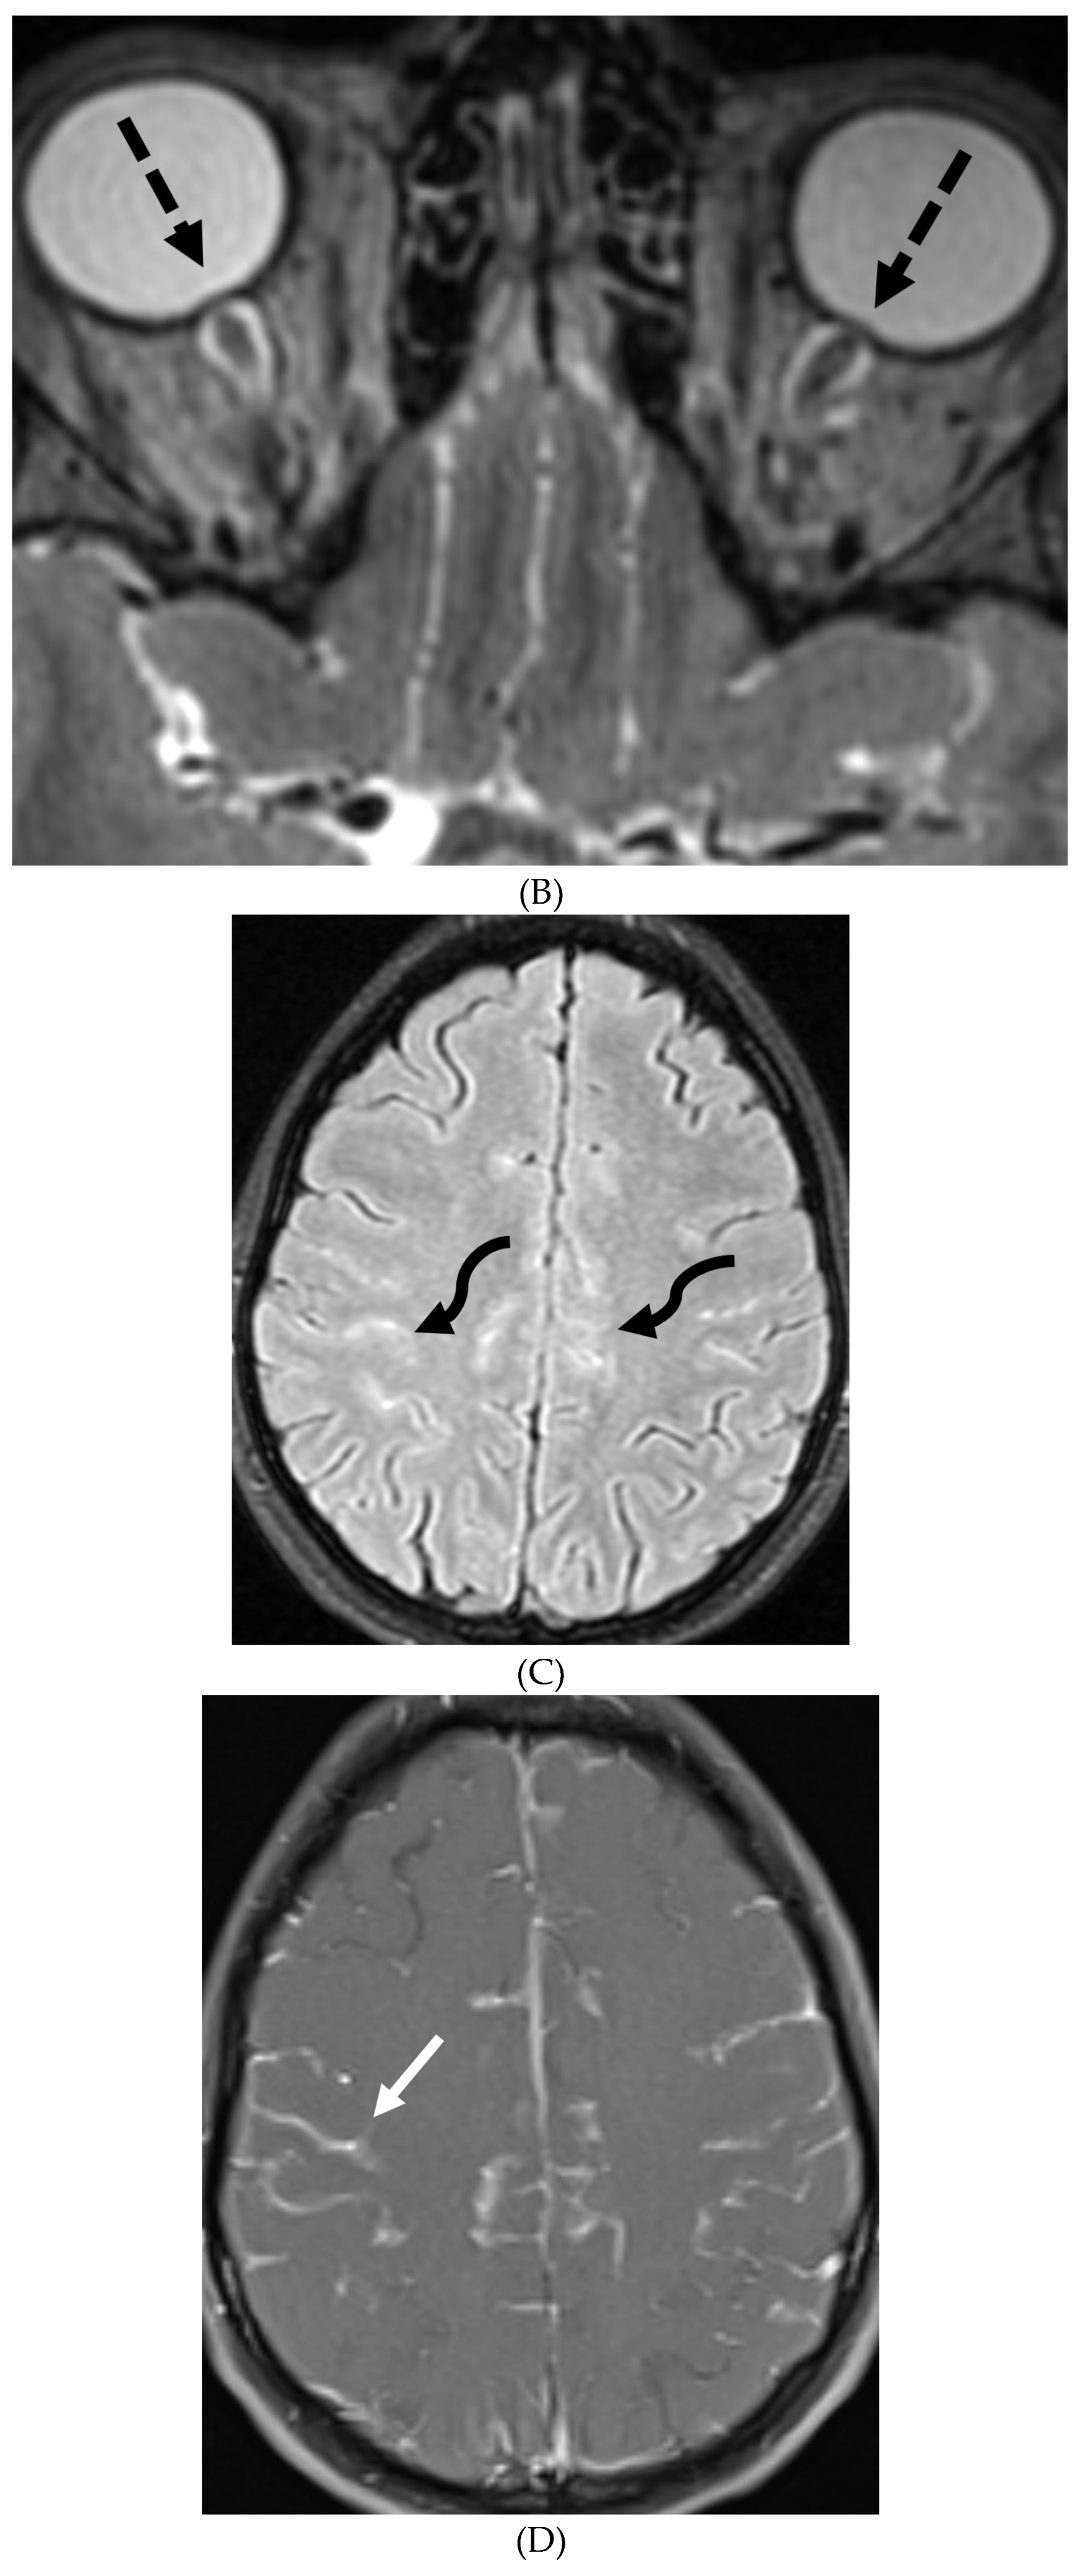

ANTI-MYELIN OLIGODENDROCYTE GLYCOPROTEIN (MOG) DEMYELINATION

- Li L, Liu W, Cai Q, Liu Y, Hu W, Zuo Z, Ma Q, He S, Jin K. Leptomeningeal enhancement of myelin oligodendrocyte glycoprotein antibody-associated encephalitis: uncovering novel markers on contrast-enhanced fluid-attenuated inversion recovery images. Front Immunol. 2023 Jun 20;14:1152235. PMID: 37409120; PMCID: PMC10318903. [CrossRef]

- Shahriari M, Sotirchos ES, Newsome SD, Yousem DM. MOGAD: How It Differs From and Resembles Other Neuroinflammatory Disorders. AJR Am J Roentgenol. 2021 Apr;216(4):1031-1039. Epub 2021 Feb 17. PMID: 32755221. [CrossRef]

- Gadde JA, Wolf DS, Keller S, Gombolay GY. Rate of Leptomeningeal Enhancement in Pediatric Myelin Oligodendrocyte Glycoprotein Antibody-Associated Encephalomyelitis. J Child Neurol. 2021 Oct;36(11):1042-1046. PMID: 34547933; PMCID: PMC9054459. [CrossRef]

- Valencia-Sanchez C, Guo Y, Krecke KN et al. Cerebral Cortical Encephalitis in Myelin Oligodendrocyte Glycoprotein Antibody-Associated Disease. Ann Neurol. 2023 Feb;93(2):297-302. Epub 2022 Dec 2. PMID: 36372941; PMCID: PMC10107670. [CrossRef]